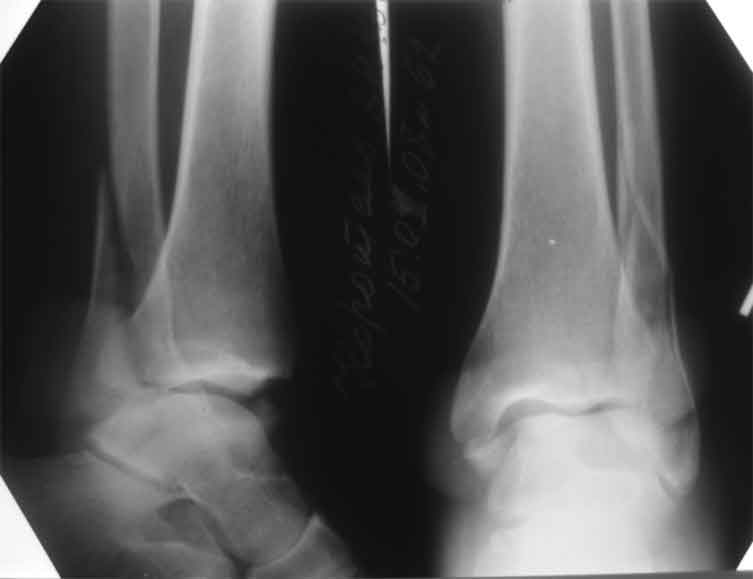

Больному всего 42, сохранный сустав, за 1.5-2 месяца сустав еще не успел "выработаться".

Каждый, представляющий что-то на сайте, особенно из крупных центров, на которых равняются ЦРБ и все остальные, должен знать, что без полного обследования со стандартными снимками нет смысла дискутировать, теряется интерес к случаю.

В данный момент больной из категории "фиксируемых

переломов" переходит в категорию "плановых", т.е.

сейчас без спешки, согласно "стандартных"

рентгенологических обследований можно планировать

восстановление.

К тому времени несросщиеся кости консолидируются,

потом легче произвести расчеты по высоте малоберцовой и выбору типа остеотомии.

Здесь представлено решение похожей проблемы. Больной в течение года лечился консервативными мерами, и боли в голеностопе были основным показанием к операции.